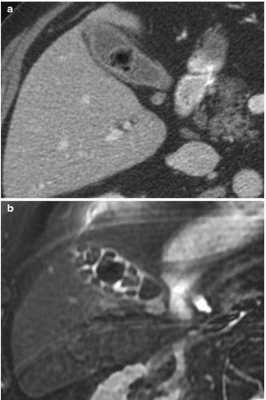

КТ (А) и МРТ(В) - картина холестериновой гранулемы

Эта дилемма волнует многих пациентов, но вид исследования выбирает лечащий врач, опираясь на результаты предыдущей диагностики и на конкретные жалобы. Отказываться от КТ уха из-за ложных соображений о вреде процедуры не стоит, современные мультидетекторные томографы позволяют минимизировать влияние лучевой нагрузки для большей категории лиц (исключение - беременные и дети, не достигшие 14 лет). В ряде наблюдений, особенно, если визуализируется опухолевый процесс, может понадобиться и МРТ, и КТ уха - эти способы взаимодополняют друг друга. Выполнение магнитно-резонансного сканирования обосновано, если после проведенной КТ остались сомнения в диагнозе. МРТ лучше демонстрирует менингоцеле, холестеатому, неврит лицевого нерва, внутричерепную патологию, вызванную процессами в среднем ухе, что не всегда показывает компьютерная томография высокого разрешения. КТ среднего уха часто не способна визуализировать степень возможной облитерации улитки после перенесенного воспаления или отдаленные последствия перелома височной кости. Точная оценка состояния имеет решающее значение для планирования кохлеарной имплантации.

Вид конкрементов у одного и того же пациента в желчном пузыре при КТ (а) и МРТ (b)